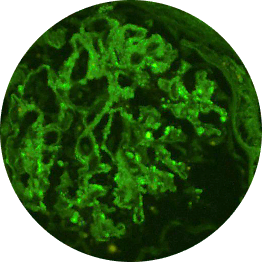

Immunofluorescence

Distinguishes between C3G and primary IC-MPGN, detecting glomerular deposition of C3 through staining of C3 fragments and/or Ig2,6,21

C3 deposits

(C3G)

C3/Ig deposits

(IC-MPGN)

C3G vs primary IC-MPGN under immunofluorescence

Histological analyses uncover disease activity and kidney damage in C3G and primary IC-MPGN. Under immunofluorescence, C3 staining intensity indicates the level of deposition of C3 breakdown products, providing diagnostic confirmation of C3G.2,23

Histological evidence from patients with repeat biopsies has shown that immunofluorescent staining patterns may change over time and sometimes lead to a switch from a diagnosis of primary IC-MPGN to C3G, or vice versa.23,24

C3G

C3G is defined by dominant glomerular C3 staining (≥2 orders of magnitude [OOM] compared with other immune reactants, including Ig).2-6

Primary IC-MPGN

IC-MPGN exhibits Ig-dominant or codominant C3 deposition under immunofluorescent staining.4,6

Microscopic images: Courtesy of Patrick D. Walker, MD, Senior Renal Pathologist at Arkana Laboratories.